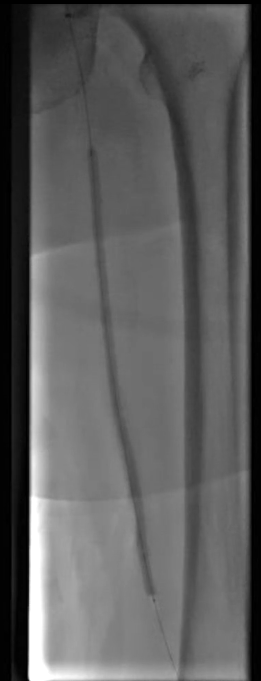

入路选择:采用右侧翻山入路,选用6F 55cm长鞘建立操作通道。

股浅动脉开通策略:计划以双向开通方式处理股浅动脉闭塞段,备逆穿技术;操作器械选用V18导丝、支撑导管,预扩张阶段使用4.0×150mm PTA球囊。